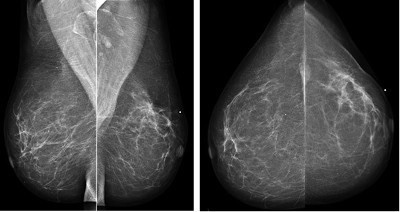

- Diffusely invasive carcinoma:

- Has a mammographic appearance of diffuse architectural distortion:

- Usually involving a large area, often larger than a lobe:

- With no central tumor mass and no calcifications:

- It sometimes has the appearance of a “spider’s web” as shown in the Image

- Forms concave contours with the surrounding fat in a manner similar to normal fibroglandular tissue (Images)

- The imaging findings of diffusely infiltrating breast cancer are strikingly different:

- From the imaging findings of breast cancers originating either from the terminal ductal lobular units (TDLUs) or the lactiferous ducts:

- Suggesting that it may have a different site of origin